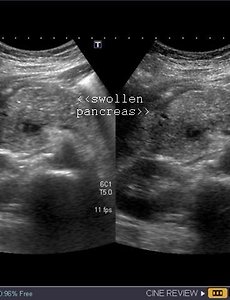

Acute pancreatitis Acute pancreatitis is sudden inflammation of the pancreas that may be mild or life threatening but usually subsides. Gallstones and alcohol abuse are the main causes of acute pancreatitis. Severe abdominal pain is the predominant symptom The pancreas is visualized nicely in the above ultrasound images and appears swollen, edematous and hypoechoic. These findings suggest acute pancreatitis. If le.. 2009. 9. 4. 이전 1 다음